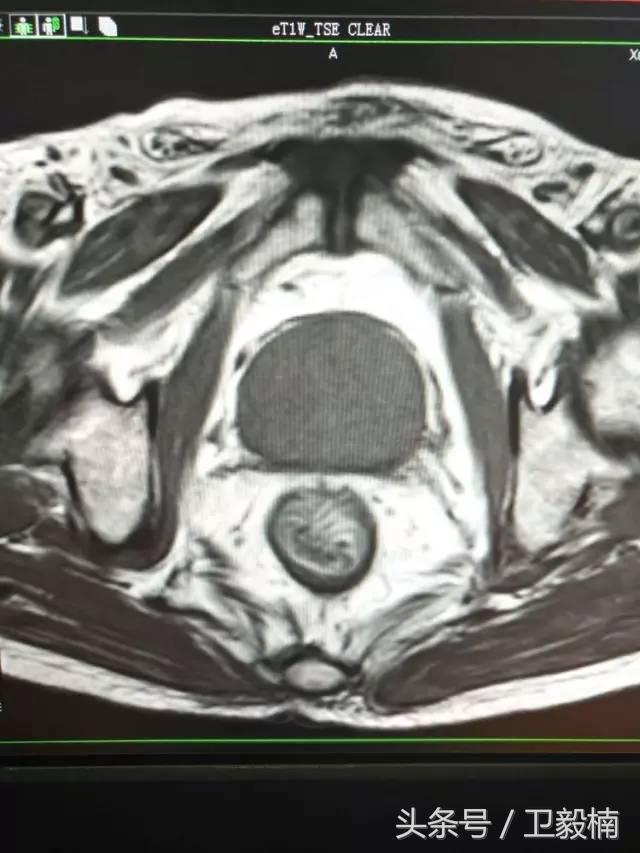

七、子宫肌瘤、子宫腺肌症、宫外孕、输卵管阻塞引起的不孕症等妇产科疾病;

(3)应用栓塞术治疗海绵状血管瘤,蔓状血管瘤,子宫肌瘤,骨肉瘤,鼻咽部纤维血管瘤等。

(2)应用栓塞术或经输卵管注入硬化剂治疗宫外孕。